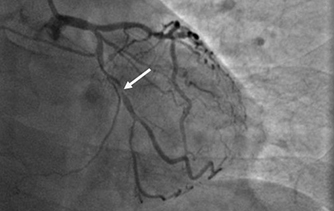

近日,河北醫(yī)科大學(xué)附屬燕達(dá)醫(yī)院心血管內(nèi)三科成功完成一例非常特殊的手術(shù)——冠心病三支病變微創(chuàng)介入完全血運(yùn)重建術(shù)?;颊呃钕壬谛牟〔∽儤O其嚴(yán)重,全部三支主干動(dòng)脈均重度狹窄,各處求診均被告知無(wú)法微創(chuàng)介入手術(shù),只能開(kāi)胸搭橋。拒絕開(kāi)胸的李先生慕燕達(dá)醫(yī)院心血管內(nèi)三科北京安貞醫(yī)院專家團(tuán)隊(duì)之名,就診于燕達(dá)醫(yī)院,由翟光耀主任為其行 “一站式”手術(shù),一 次 性完成三支動(dòng)脈的修復(fù)!手術(shù)非常成功,李先生術(shù)后恢復(fù)良好,滿意出院。   震驚 患者三支血管均90-99%狹窄 ..